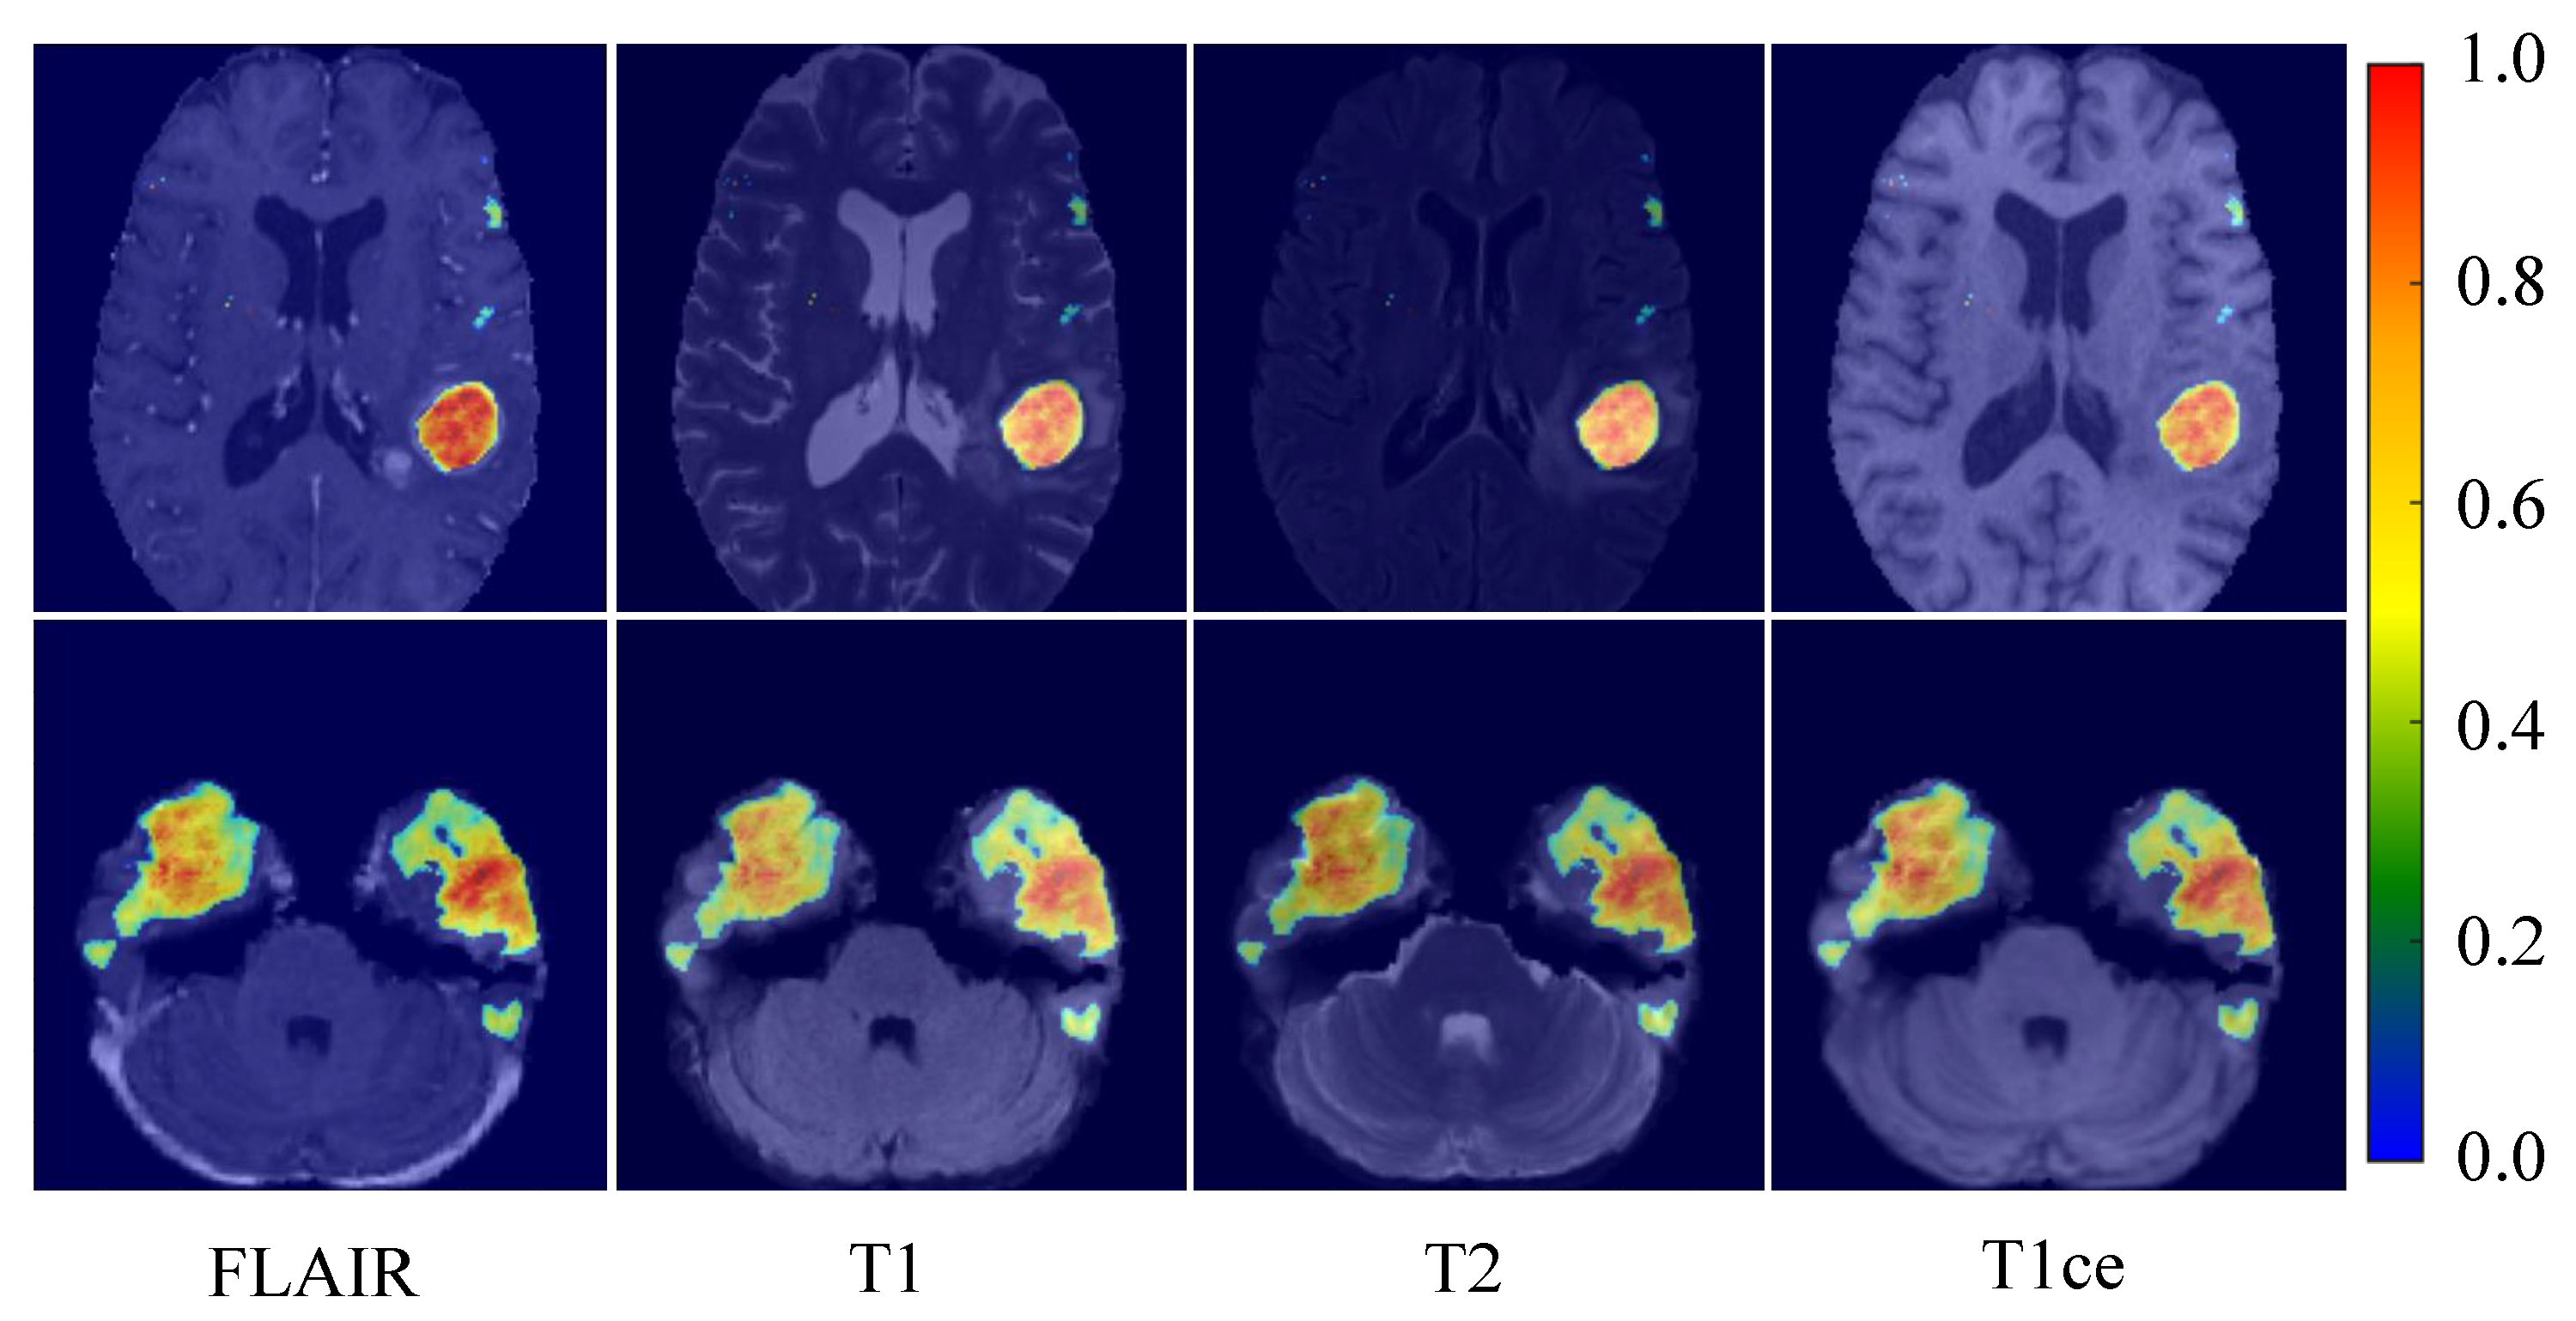

4.3. Multi-Modal Thermogram and Characteristic Graph Analysis

This investigation explored the efficacy of the proposed model in segmenting brain tumors and its adeptness at discerning the intricacies of multi-modal magnetic resonance imaging (MRI) data. To achieve this objective, heatmaps were generated for each of the four MRI modalities: FLAIR, T1, T2, and T1ce. These heatmaps, as illustrated in Figure 9, intricately detail the model’s focus areas during the prediction of tumor regions, showcasing its consistent capability to pinpoint tumor locations across different imaging modalities. The arrangement of heatmaps in the top row for the FLAIR, T1, T2, and T1ce modalities shows that the model keenly concentrates on areas with significant tumor presence across all modalities despite their distinct imaging characteristics, which underscores the model’s remarkable skill at amalgamating multi-modal information to localize tumors accurately.

Figure 9. Heatmaps of the brain tumor segmentation model under different MRI modalities. In the heatmap, hot zones (from red to yellow) represent areas with a high probability of tumor presence per the model’s prediction. In contrast, cold zones (blue) indicate areas with a lower prediction probability.